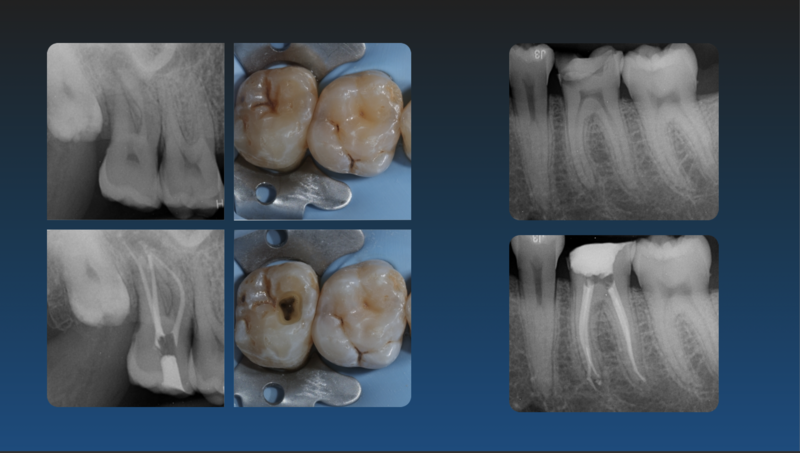

Je dispose de mon propre matériel et d'un portfolio de cas cliniques pour illustrer la qualité de mes interventions.